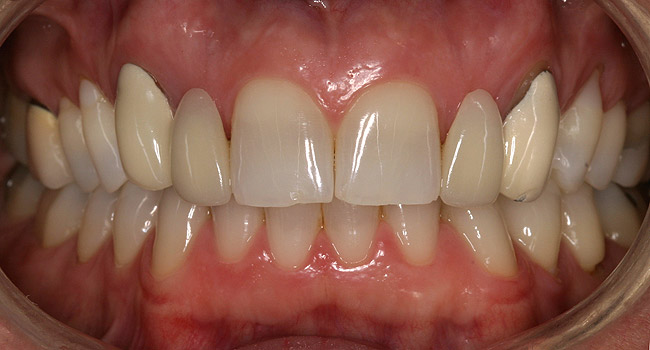

Figure 7a  Recently extracted tooth No. 9 (upper left central incisor), grafted site. Heavily treated adjacent teeth Nos. 8 and 10 with three-quarter porcelain laminate veneers.

Figure 7a

Figure 7b  Recently extracted tooth No. 9 (upper left central incisor), grafted site. Heavily treated adjacent teeth Nos. 8 and 10 with three-quarter porcelain laminate veneers.

Figure 7b

Figure 7c  Completed single all-ceramic screw-retained implant crown site on tooth No. 9, revised porcelain three-quarter laminate veneers for teeth Nos. 8 and 9, cemented with Kerr NX3 Nexus¬Æ Third Generation Dual Cure Resin cement.

Figure 7c

Figure 7d  Completed single all-ceramic screw-retained implant crown site on tooth No. 9, revised porcelain three-quarter laminate veneers for teeth Nos. 8 and 9, cemented with Kerr NX3 Nexus¬Æ Third Generation Dual Cure Resin cement.

Figure 7d

Figure 7e  Completed single all-ceramic screw-retained implant crown site on tooth No. 9, revised porcelain three-quarter laminate veneers for teeth Nos. 8 and 9, cemented with Kerr NX3 Nexus¬Æ Third Generation Dual Cure Resin cement.

Figure 7e

When a patient presents with a missing anterior tooth and heavily treated adjacent teeth, although conceptually an FPD option may seem the most appropriate choice, it can be argued that it would not be the most favorable option. If long-term treatment outcome is a strong motivator for the patient, then a treatment plan that includes individual restored units would be the more appropriate choice. Consequently, the patient would most likely have improved benefit with a single implant-supported restoration and treating the adjacent teeth as separate, single units (Figure 7).